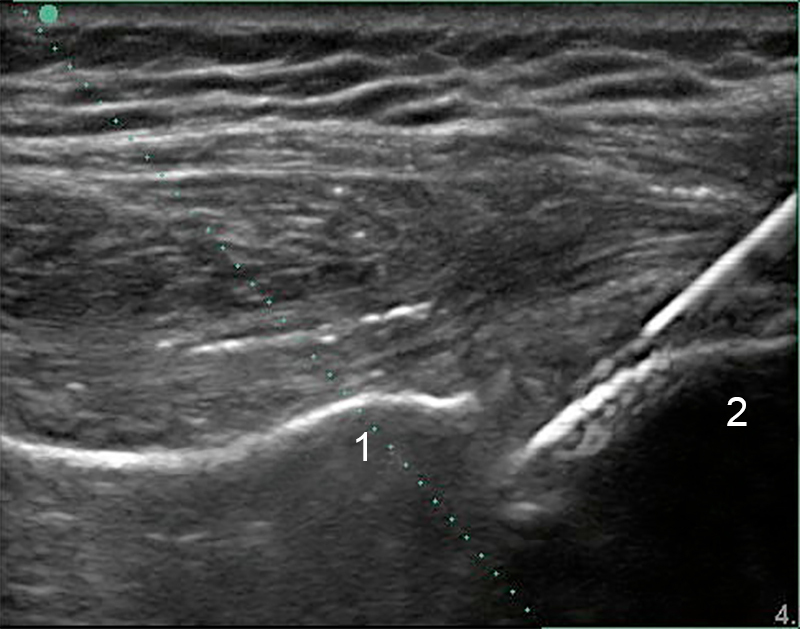

开启 MBe 的肩部后盂肱注射图像

关节窝

肱骨头